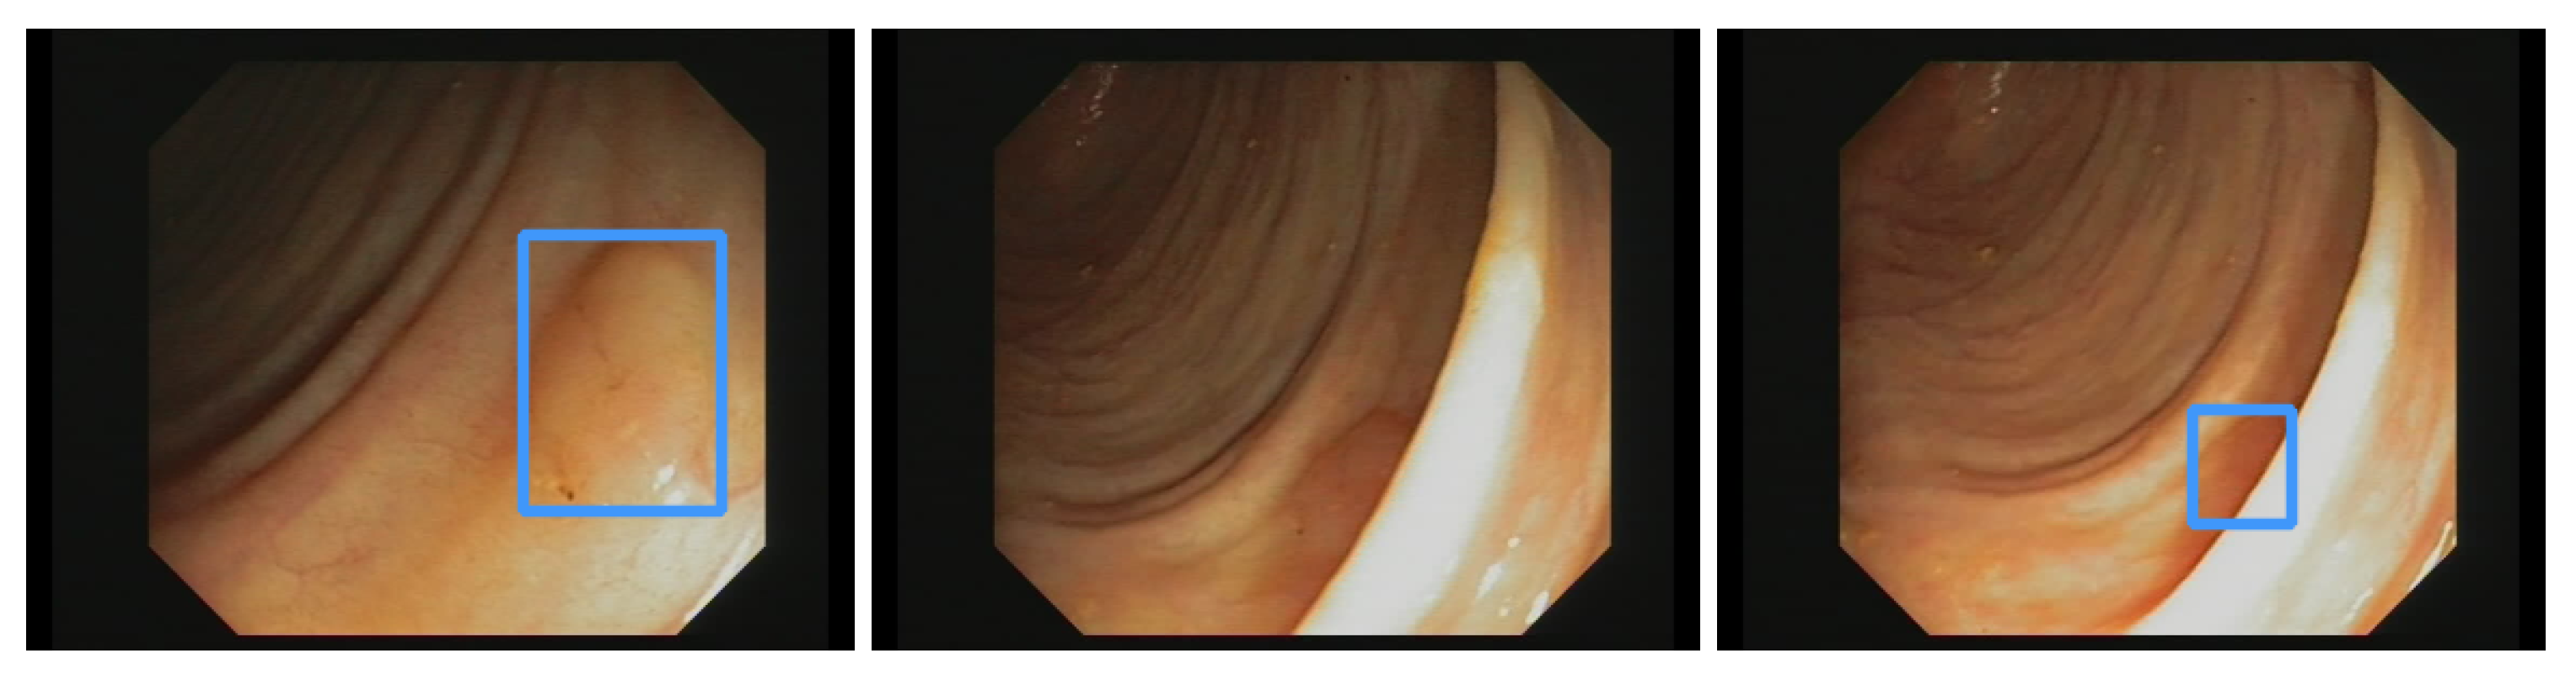

Additionally, the polyp-detection system was publicly funded and developed by computer engineers and endoscopists in the same workgroup to ensure high-quality polyp detection. Figure 1 shows the results of the polyp-detection system. To overview existing work and properly allocate our paper in the literature, we describe a brief history from general polyp detection with handcrafted features to state-of-the-art polyp detection with deep learning techniques.

3.2. EndoData Evaluation

Our own validation set (EndoData) allows us to detect polyps more precisely and accurately. Table 8 shows an overview of the videos in the dataset and Figure 13 shows examples of the dataset. The EndoData dataset records sequences as the polyp appears in the scene. Therefore, polyps are marked precisely with their first appearance. In comparison, the polyp sequence of the CVC-VideoClinicDB dataset might not start when the polyp is already detected. Those early seconds are crucial as the gastroenterologist has to identify and not miss the polyp during this time. If the polyp is not detected in the early sequence, it increases the risk of missing it. As we like to focus on this early detection, we introduce a second metric that can just be evaluated with a dataset like ours. This metric marks the seconds from first seeing the polyp to first detecting the polyp. We call it first detection time (FDT). Additionally, we compute the FPs and the false positive rate (FPR) per video (Table 10 and Table 11).